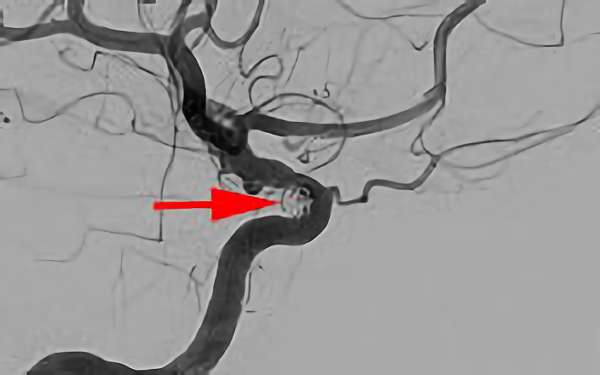

No.1631 手術前

No.1631 手術中

No.1631 手術後